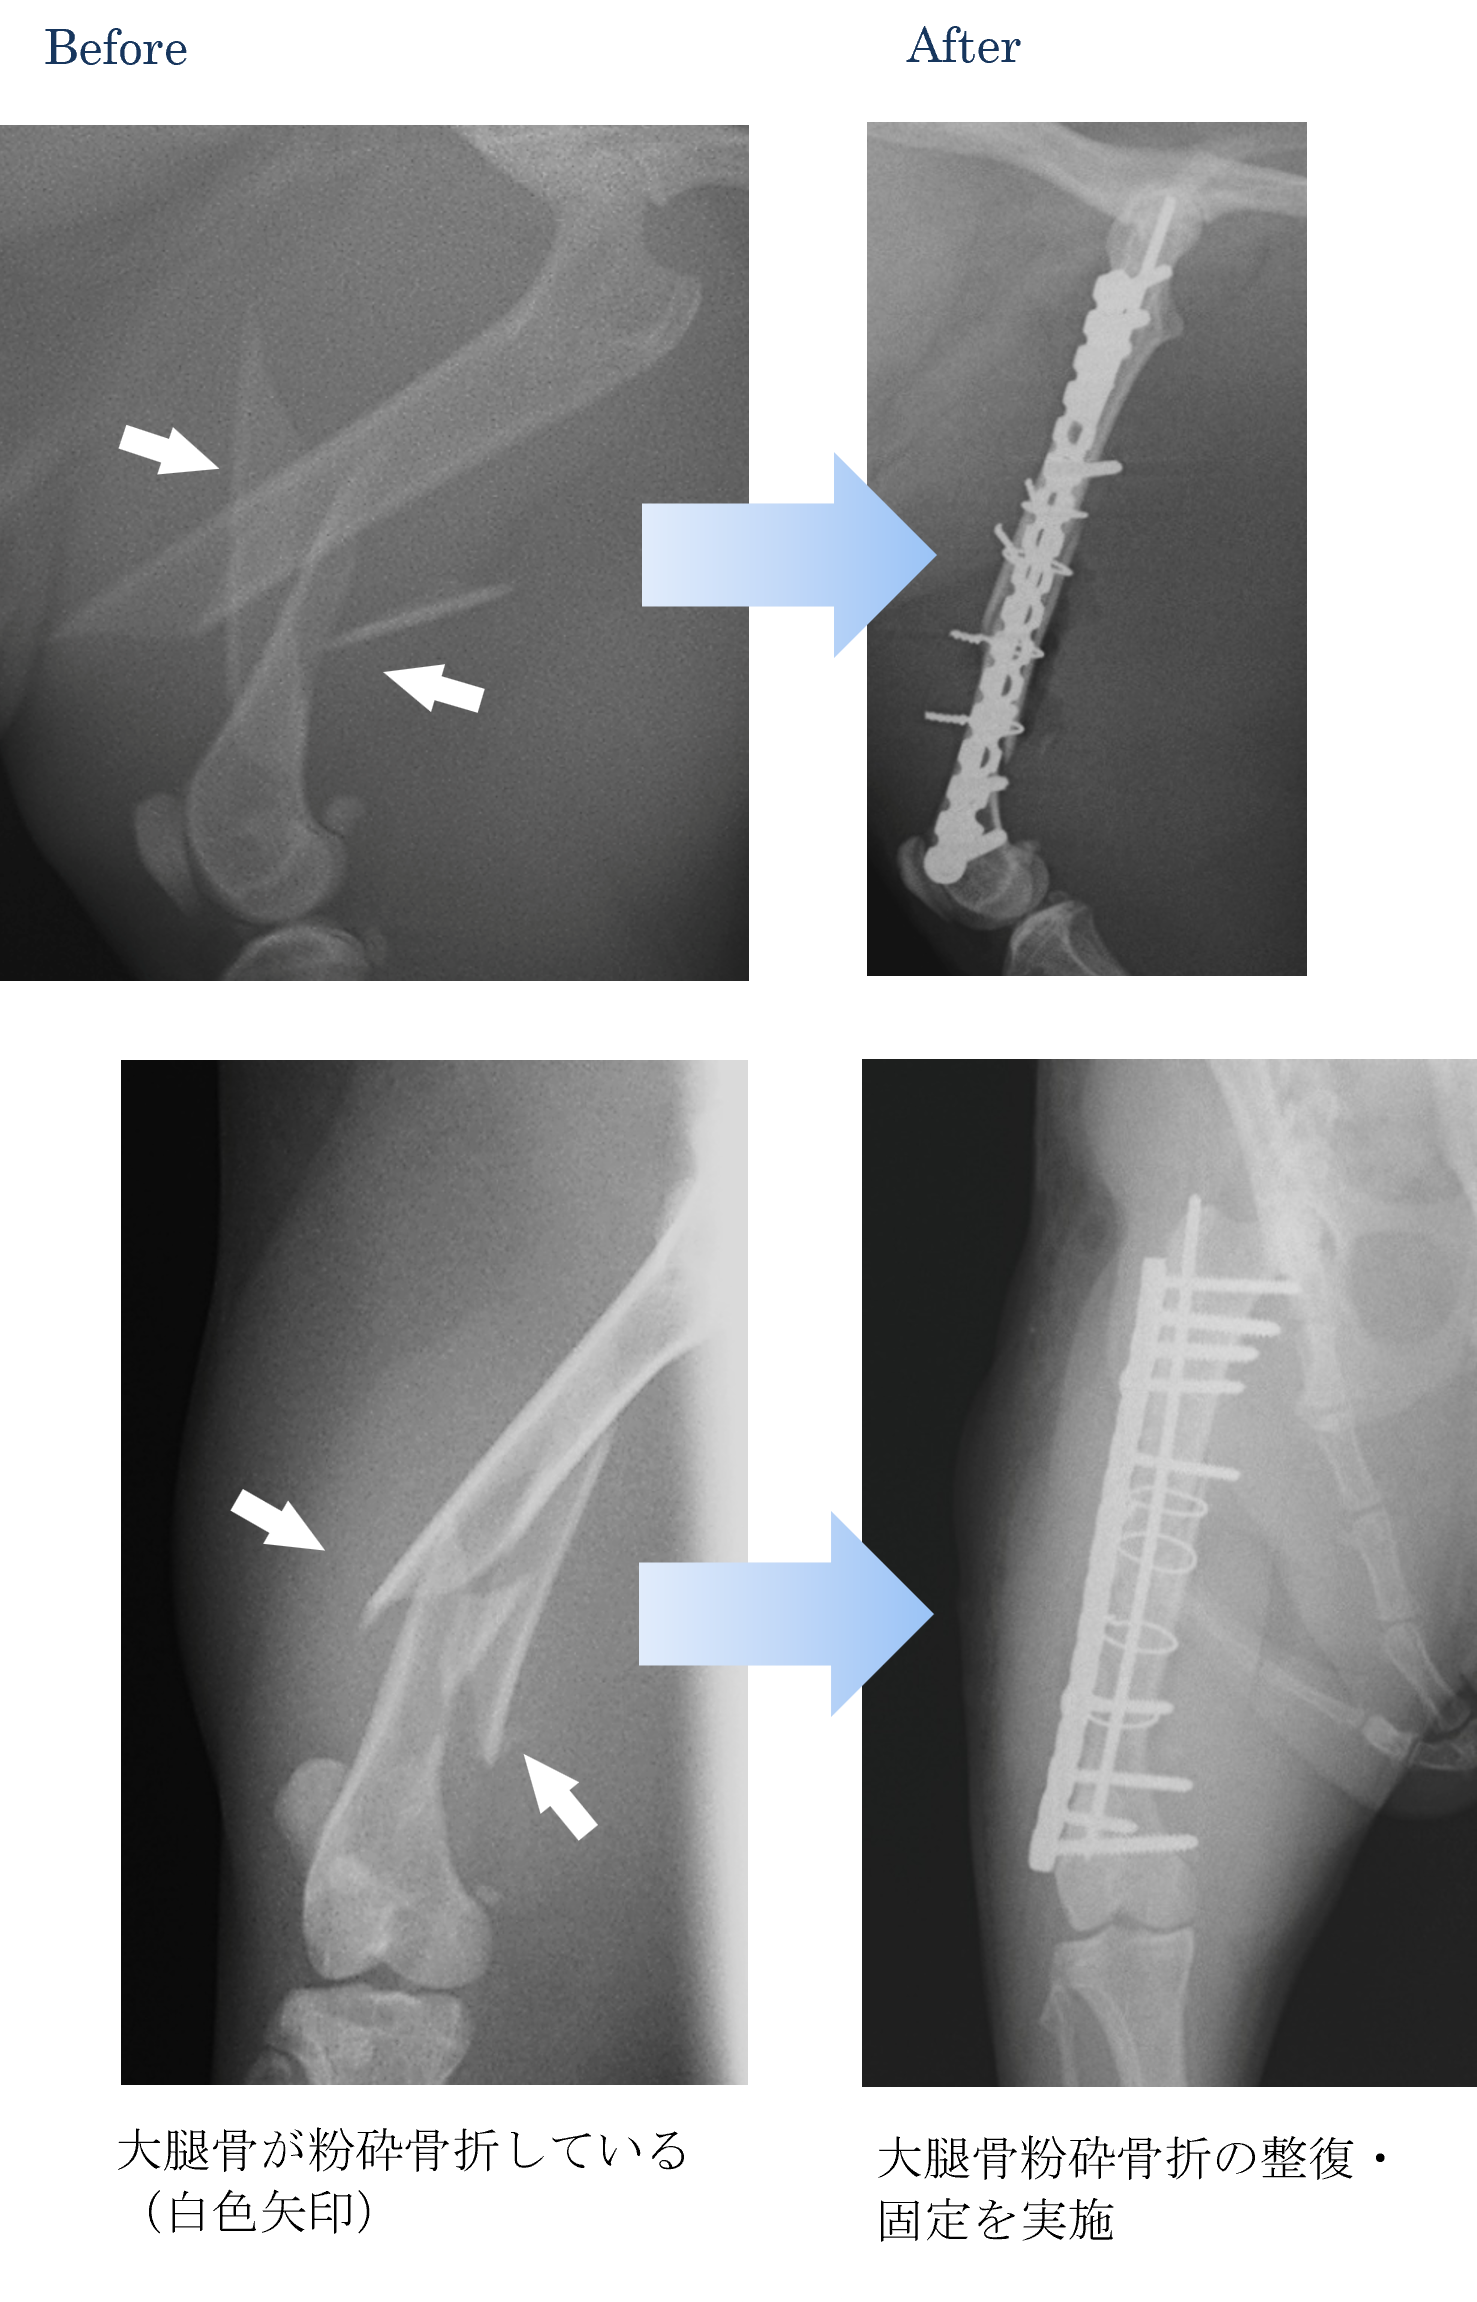

各種検査より、大腿骨(太ももの骨)の粉砕骨折と診断しました。

ご家族と相談して手術で整復して固定を実施することになりました。

手術後は以前と同じように走ったり遊んだりすることができるようになりました。